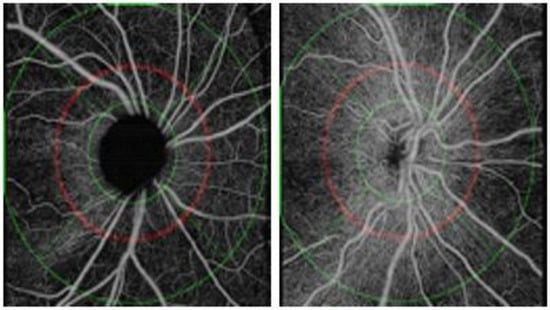

3.2. Qualitative Analysis